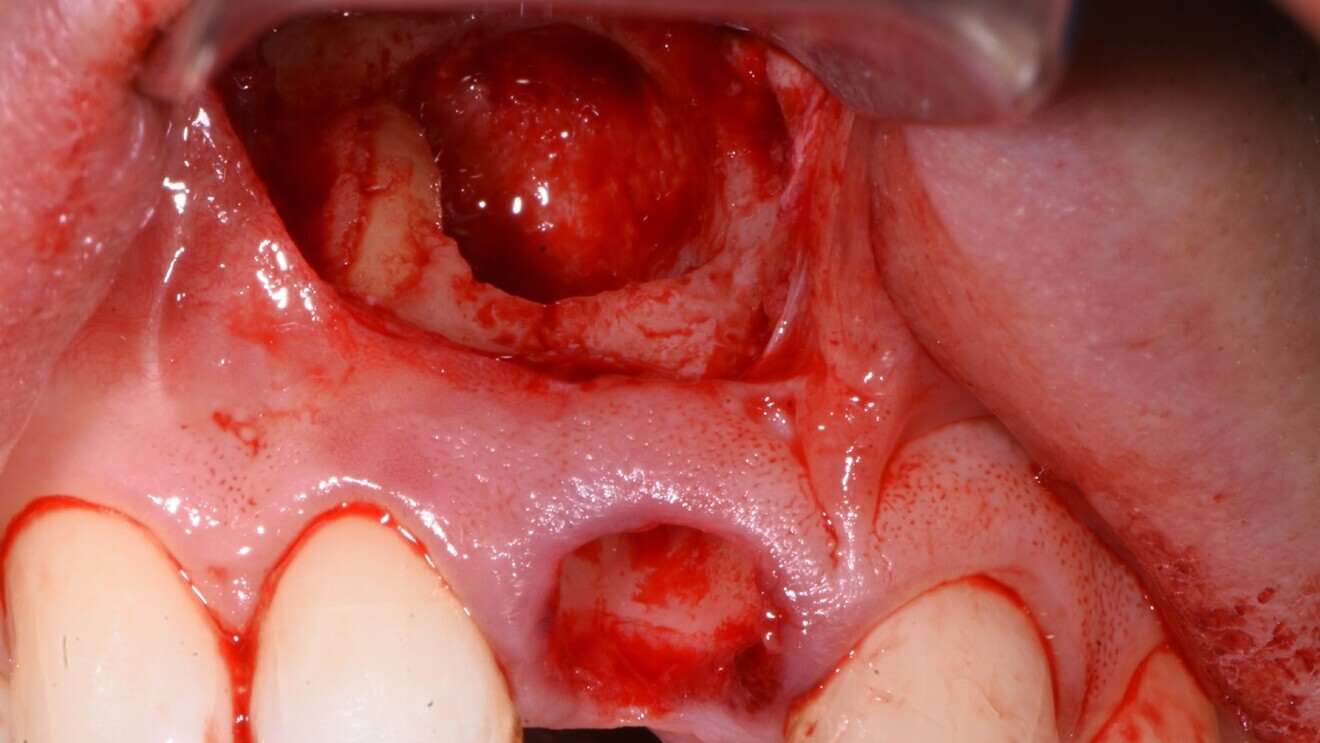

Fig. 5: Extraction socket with the infra-bony cyst cavity exposed.

An atraumatic extraction protocol was used, involving initial luxation with a periotome and a rotational rather than facial-palatal method of displacement, thereby preserving the facial plate. Once the tooth had been extracted, a sub-sulcular envelope incision was used to gain access to the lesion, and the cyst was enucleated and the surrounding bone curetted and decontaminated (Fig. 5). A surgical guide was used to ensure the optimal position of the implant (Fig. 6), and the apical cutting threads of the PrimeTaper EV implant (Fig. 7) ensured that the implant engaged effectively with the apical bone, but the insertion torque only reached 20 Ncm owing to the large cyst-related cavity and the resulting lack of significant initial bone-to-implant contact. The baseline ISQ value was 61 and 65 in the facial-palatal and mesiodistal directions, respectively (Fig. 8), but in my experience, this combination of torque and ISQ value indicated that the implant was suitable for immediate loading, since the torque was ≥ 20 Ncm and the ISQ value was ≥ 65 in one direction.